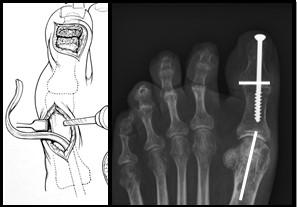

Jones Procedure

Bij de Jones procedure wordt de lange strekpees van de grote teen verplaatst van het eindkootje naar het middenvoetsbeentje van de grote teen. De beide kootjes van de grote teen worden aan elkaar vastgezet met een schroef. Deze procedure zorgt ervoor dat de strekpees van de grote teen de teen niet meer doet klauwen maar zorgt juist voor een omhoogwaartse beweging van de grote teen. Dit gaat weer de holvoet tegen.

Figuur 5: Op het linker plaatje is de grote teen zichtbaar. Er worden 2 littekens gemaakt. De pees wordt losgehaald bij het eindkootje en door het middenvoetsbeentje gevlochten door een boorgat. Op de rechter foto is de schroef zichtbaar die beide kootjes aan elkaar verbindt. Deze wordt vanuit het puntje van de teen geboord middels een (klein) 3e litteken. De witte streepjes geven de locatie van de andere 2 littekens aan.